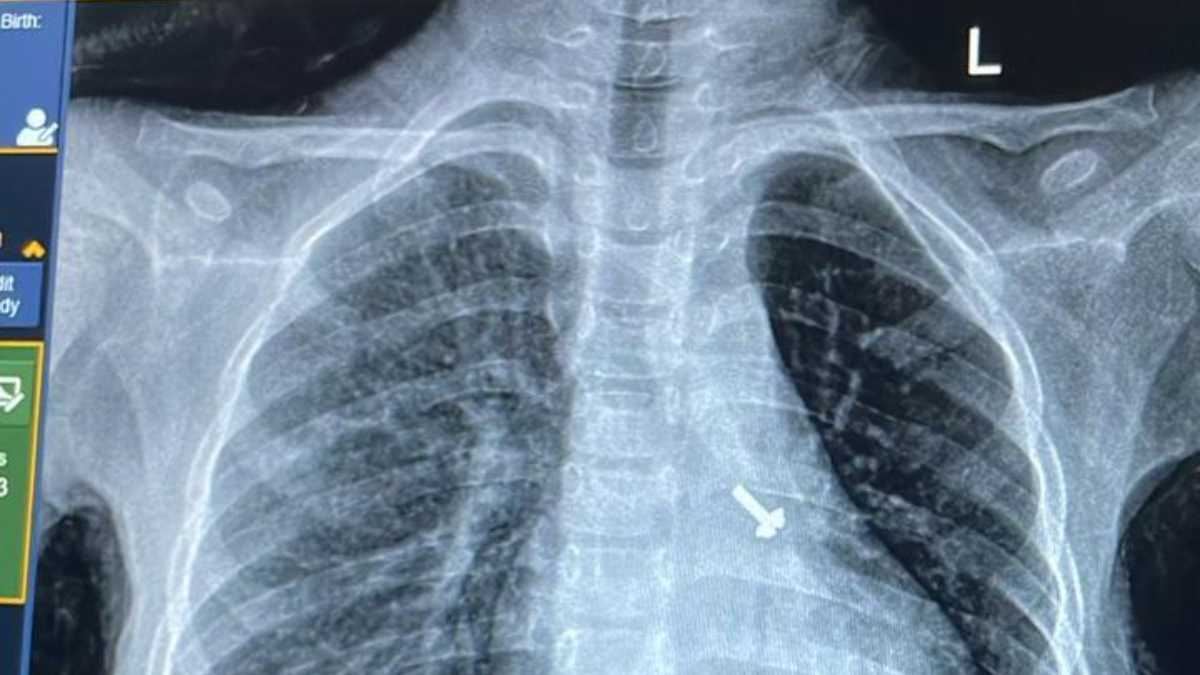

07 वर्ष के बच्चे के फेफड़े में फंसे पेंच को निकालकर एम्स के चिकित्सकों ने दिया जीवनदान

ऋषिकेश: अखिल भारतीय आयुर्विज्ञान संस्थान, ऋषिकेश के पल्मोनरी मेडिसिन विभाग की ओर से संचालित ब्रोंकोस्कोपी […]